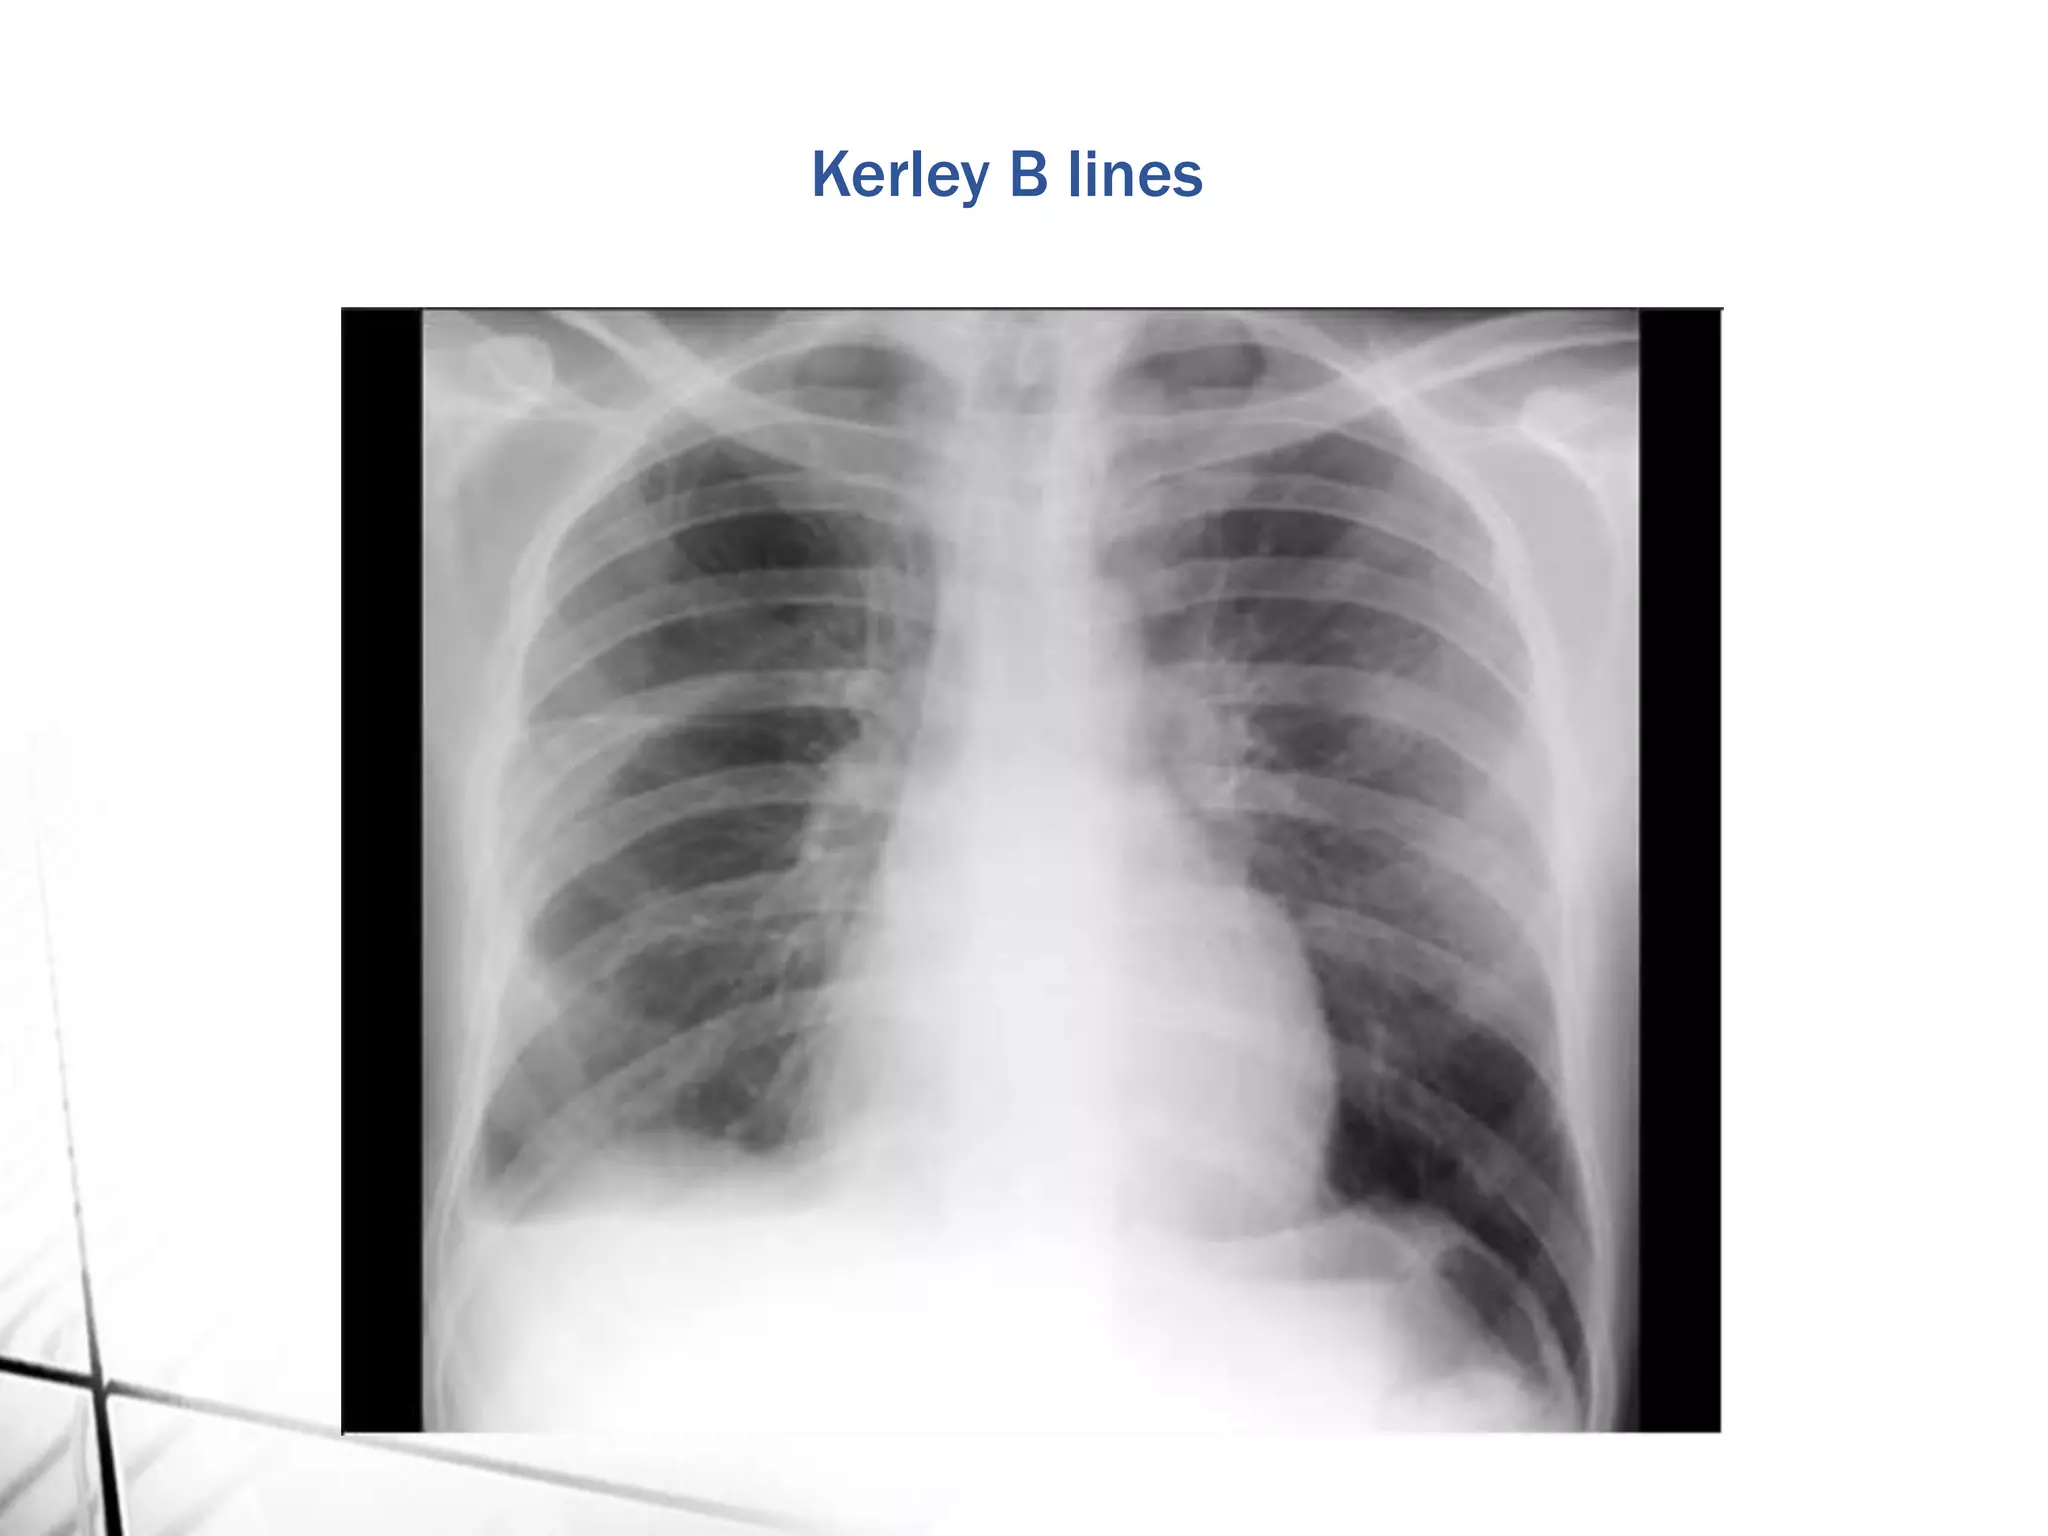

Kerley B lines